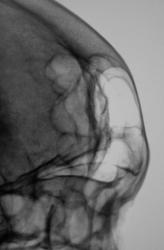

А, что "это" за уплотнения.

Уплотнения? Возможно эностозы.

Эностозы???

Может тогда только участки локального остеосклероза? Ведь..."Эностоз (enostosis; эн- + греч. osteon кость + -оз) — заращение костномозговой полости костной тканью"....

Да, наверно, правильно участки остеосклероза.